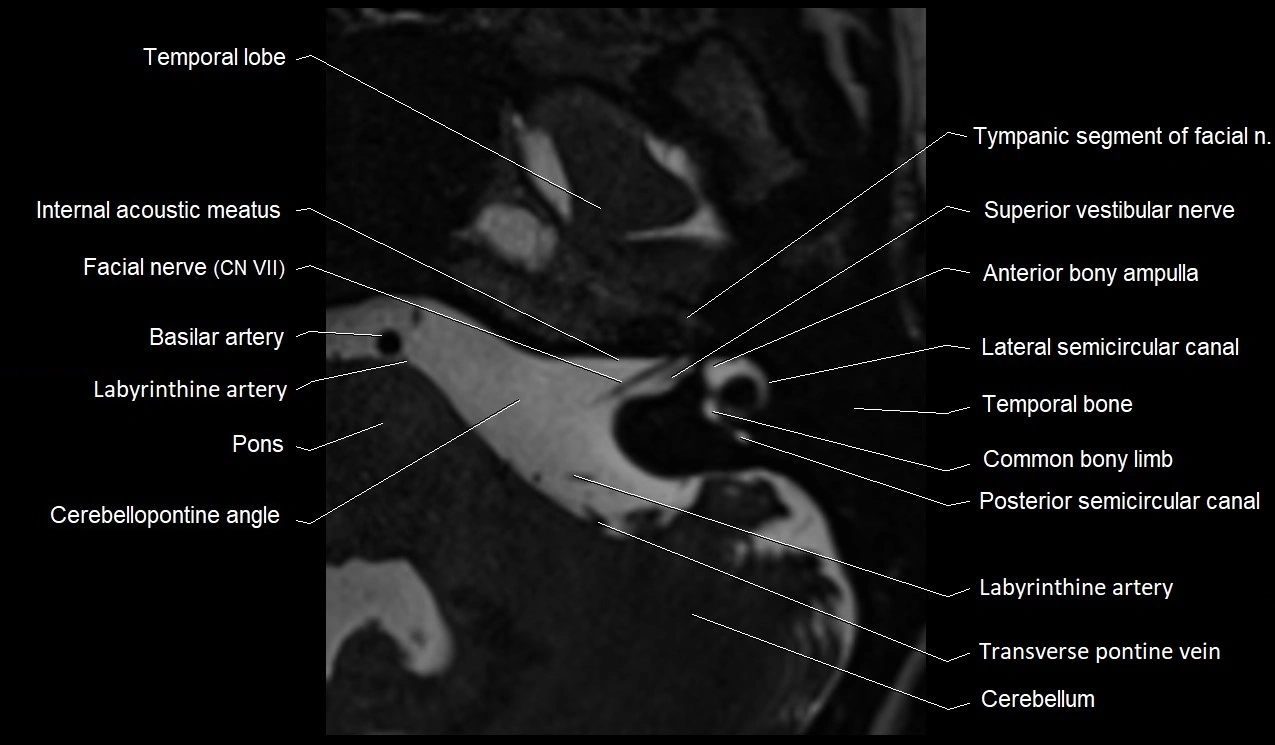

MRI Appearance

• The abducens nerve is a small, thin, linear structure

• Best visualized on high-resolution T2-weighted 3D MRI sequences (e.g., FIESTA or CISS)

• Seen as a hypointense (dark) line running from the brainstem at the pontomedullary junction, traversing the prepontine cistern, and entering Dorello’s canal under the petrosphenoidal ligament, then into the cavernous sinus, and finally the orbit

• May be challenging to visualize in standard MRI due to its small size

• Pathology may be inferred by absence, displacement, or enhancement of the nerve